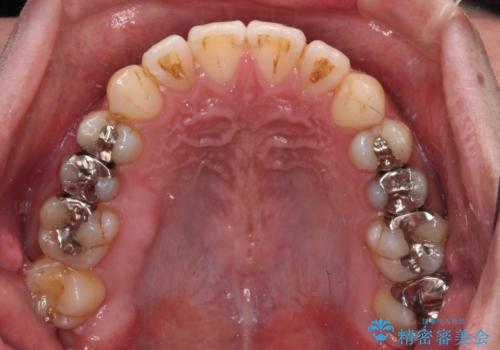

銀歯については、矯正治療により咬合関係を改善し、矯正治療後半に修復治療を行うこととしました。

修復治療後に細かい部分をインビザラインで再度仕上げるプランとしました。

銀歯のセラミック治療が1番の希望であったため、ここまで歯列がきれいに整うとは思ってなかったようで、大変喜んでいただけました。